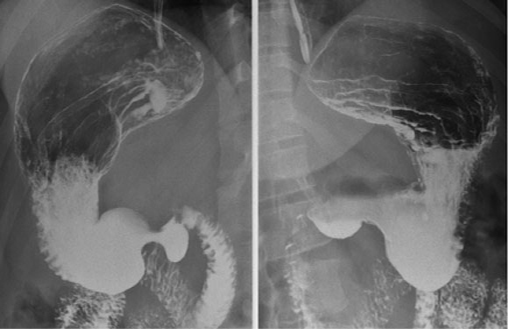

image TOGD de oesophage (

angle de His ) et estomac normale |

Images normales de estomac , bulbe et

duodenum expose en serie |

Anatomie radiolologique TOGD de

l'estoma ( image radiologique normale de estomac ) :

La variation de l'aspect de l'estomac

sur TOGD est selon a la posture du patient . Aspect de

chaussure en debout et a horizontal legerement en decubitus

OAD . Normalement il y en a trois portion : Poche a

air gastrique ( gros tuberosite ) situe a superieur du

cardia , portion montant de angle de His au bord

inferieur de estomac , portion horizontale de portion

montant a pylore . L'angle de His situe entre l'oesophage et

la gros tuberosite forme un mecanisme anti-reflux . La

contraction de la grosse tuberosite vers l'antre et le

pylore entrine d'evacuation progressive du contenu vers le

duodenum . Les 4 portions duodenales encadrant la tete du

pancreas

| 1 Oesophage |

| 2 Cardia |

| 3 Angle de His |

| 4 Gros tuberosite (poche a air

gastrique ) |

| 5 Grande courbure |

| 6 Petite courbure |

| 7 Portion montant de

l'estoma |

| 8 Antre prepylorique de

estomac |

| 9 Pylore |

| 10 Bulbe |

| 11 Genu superus |

| 12 D2 |

| 13 Genu inferus |

| 14 D3 |

| 15 D4 |

| 16 Angle de Treizt |

| |